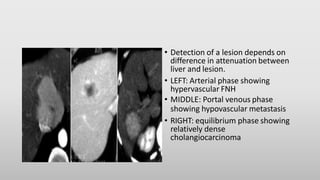

• Detection of a lesion depends on

difference in attenuation between

liver and lesion.

• LEFT: Arterial phase showing

hypervascular FNH

• MIDDLE: Portal venous phase

showing hypovascular metastasis

• RIGHT: equilibrium phase showing

relatively dense

cholangiocarcinoma